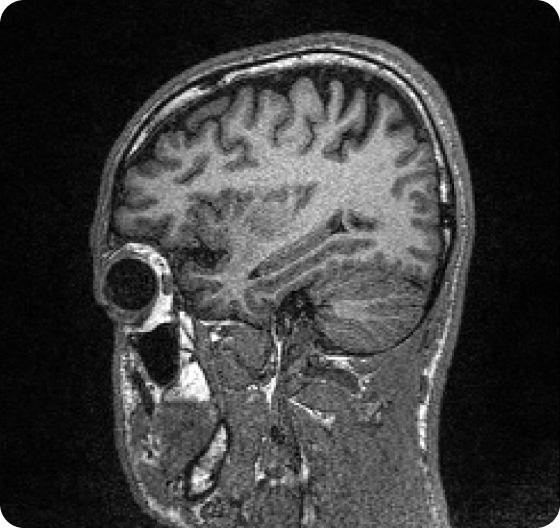

SwiftMR reduces MRI scan times. SwiftSight delivers objective, replicable brain health metrics.

Standard of care

With SwiftMR